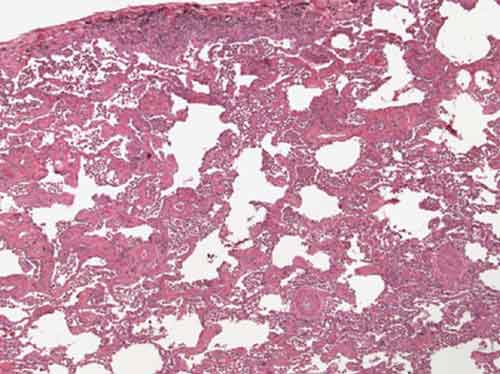

L’infiammazione e la formazione di cicatrici sono risultate ridotte tra i topi cui era stato iniettato un composto organico, una piccola molecola denominata PF-573228, che blocca questo enzima. “Il nostro studio espone uno dei meccanismi fondamentali attraverso cui un intervento meccanico puo’ influire direttamente sull’infiammazione implicata nella formazione di cicatrici”, ha detto Geoffrey Gurtner, docente di Chirurgia alla Stanford University School of Medicine. In attesa di ulteriori prove per determinare la validita’ dei risultati negli esseri umani, i ricercatori sperano che il lavoro possa aprire la strada a nuovi trattamenti delle malattie fibrotiche – disturbi causati da eccesso di cicatrici, come per esempio la fibrosi polmonare, consistente nell’accumulo di tessuto cicatriziale nei polmoni – cosi’ come delle malattie infiammatorie, a cominciare dall’artrite reumatoide.

Secondo i ricercatori, mentre ci sono dei noti meccanismi chimici che portano alla infiammazione, le forze meccaniche sono state generalmente trascurate come stimolo chiave di tale risposta biologica e come possibile bersaglio terapeutico. “Non abbiamo mai considerato l’ambiente fisico, ovvero il contesto delle forze meccaniche che tengono insieme tutte le nostre cellule, come fonte di infiammazione e fibrosi”, ha detto Gurtner. Grazie agli studi sui modelli animali, i ricercatori hanno scoperto che l’enzima, noto come chinasi di adesione focale sembra modulare le molecole proteiche usate dalle cellule per comunicare tra loro. In studi in provetta, il tessuto cicatriziale dei topi privati di questo enzima non ha risposto normalmente agli stimoli meccanici rilasciando livelli molto piu’ bassi di mediatori infiammatori e di tessuti cicatrizzati. I ricercatori hanno testato gli effetti dell’enzima di inibizione della molecola (PF-573228) su cellule umane che svolgono un ruolo chiave nella guarigione delle ferite e hanno scoperto che non sono state rilasciate molecole che stimolano l’infiammazione. Sono necessari ulteriori test prima di poter dire se questo approccio possa servire come base per una terapia valida. I ricercatori sperano che i risultati possano essere usati per sviluppare trattamenti per le malattie che implicano eccesso di cicatrici in tutto il corpo.